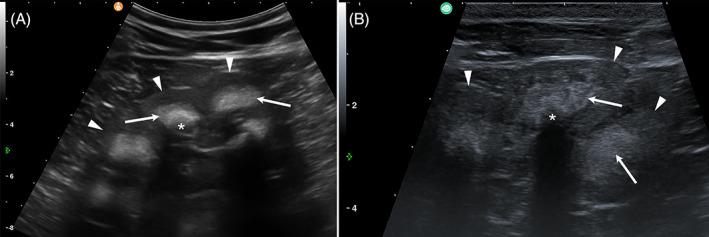

Ultrasonography revealed hyperechoic renal pyramids with multifocal distal shadowing and echogenic sediment in the urinary bladder. Necropsy revealed suppurative bronchopneumonia and urolithiasis. Histology revealed numerous nephroliths with multifocal chronic lymphohistiocytic interstitial infiltrates, fibrosis, tubular degeneration, chronic multifocal glomerulonephritis with sclerosis, and bilateral hydronephrosis. Dysplastic changes were observed in the corium of the claw and the cornea. Genetic testing identified the homozygous presence of a known MOCOS frameshift variant in the case. Both parents were heterozygous and the prevalence of carriers in genotyped Brown Swiss cattle was 1.4% (342/24337).

超声检查显示肾脏锥体呈高回声,伴有多灶性远端阴影和膀胱内回声性沉淀物。剖检显示化脓性支气管肺炎和尿石症。组织学检查显示许多肾结石,伴有多灶性慢性淋巴组织细胞间质浸润、纤维化、管状变性、双侧肾盂积水。爪的真皮和角膜有发育不良变化。基因测试确定了该病例中已知 MOCOS 移码变体的纯合存在。父母均为杂合子,在基因分型的瑞士褐牛中携带者的流行率为 1.4%(342/24337)。